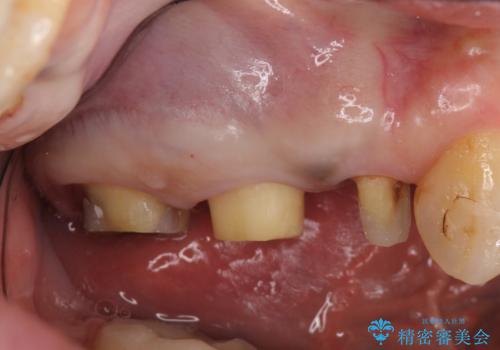

診査の結果痛みの原因は右上7番目だったため、古い樹脂と虫歯を除去後、オールセラミッククラウンによる補綴を行いました。

また右上5、6番目の歯も治療を希望されたため、オールセラミッククラウンによる補綴を行いました。

今回用いたオールセラミッククラウンはジルコニアフレームという白い素材の上にセラミックを盛っているため、審美性が非常に高いのが特徴です。

また、ジルコニアは人工ダイヤモンドの材料にも使われているほど高い強度を持っており、そのためオールセラミッククラウンは審美性だけでなく、奥歯やブリッジの補綴も可能とするクラウンです。